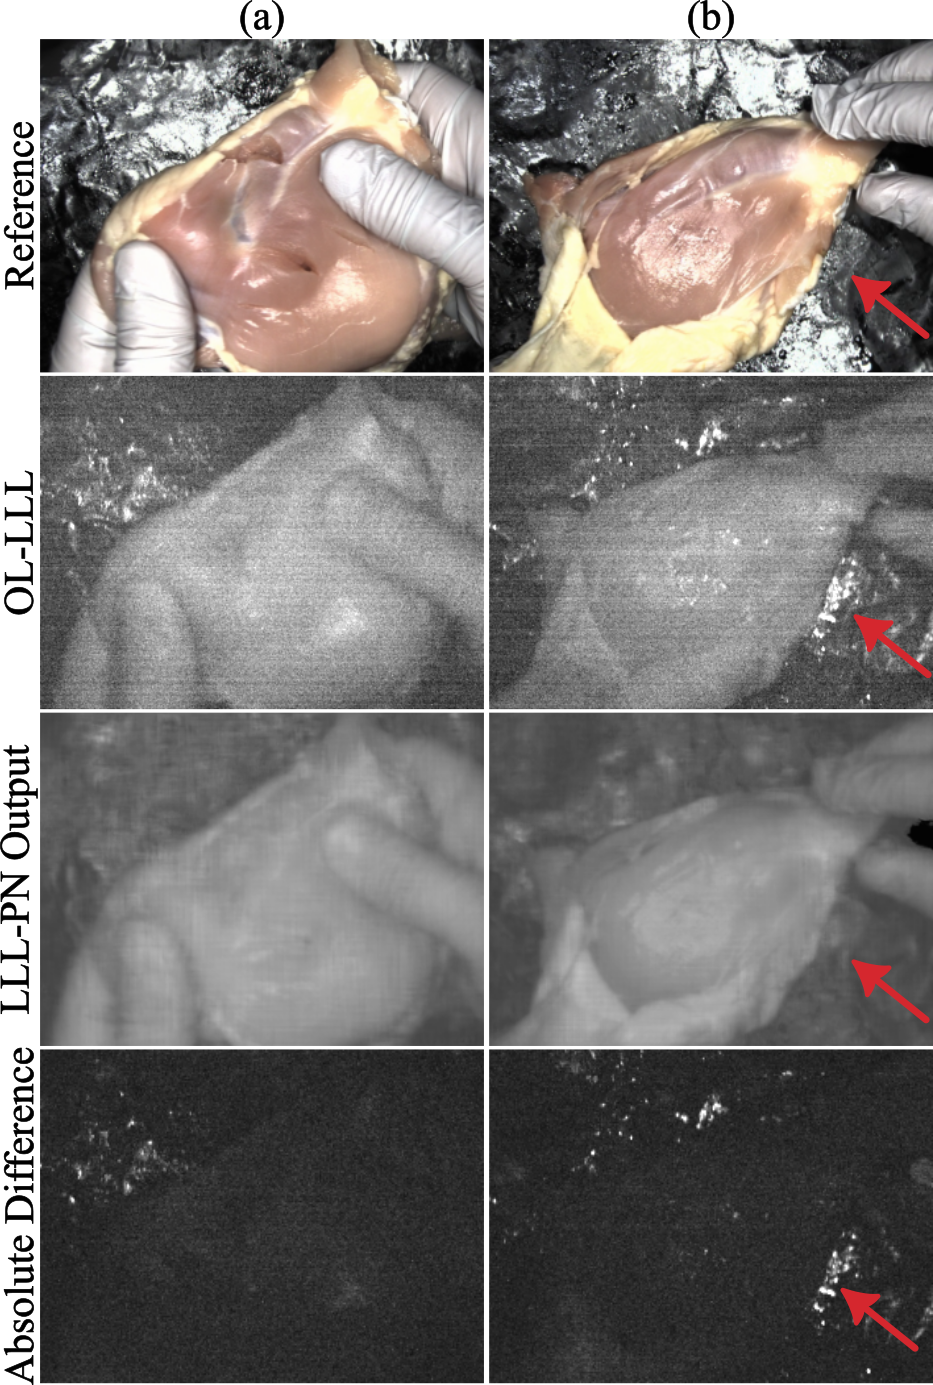

Figure 4: LLL and LLL-PN: This figure shows examples from OL-LLL and our corresponding LLL-PN predictions. The last row shows the absolute difference between the LLL frame and prediction. The LLL-PN is able to correctly predict most of the large structure leaving shot and read noise. The LLL-PN struggles with features that are uncorrelated to the reference image; for example, specular reflections (red arrow) are particularly difficult.

Fig. 4 shows example qualitative results, note that when predicted LLL is subtracted from the noisy LtLLsubscriptsuperscript𝐿𝐿𝐿𝑡L^{LL}_{t}italic_L start_POSTSUPERSCRIPT italic_L italic_L end_POSTSUPERSCRIPT start_POSTSUBSCRIPT italic_t end_POSTSUBSCRIPT, the result still contains read noise patterns but strong LLL spatial patterns vanish. The LLL-PN struggles to predict specular reflections which is to be expected because the laser and reference lights are not co-located so specular reflections in the FV should be very difficult to predict from the RV alone without 3D scene information. We also find that other 3D dependent structures such as shadows of hands and other tools are difficult to predict for the LLL-PN. fLLLsubscript𝑓𝐿𝐿𝐿f_{LLL}italic_f start_POSTSUBSCRIPT italic_L italic_L italic_L end_POSTSUBSCRIPT is able to account for 40%percent4040\%40 % of the total energy (L2subscript𝐿2L_{2}italic_L start_POSTSUBSCRIPT 2 end_POSTSUBSCRIPT norm) in noisy LLL frames. This coupled with our qualitative results indicate a strong ability to predict LLL. See Suppl. Sec. I-E for training details.